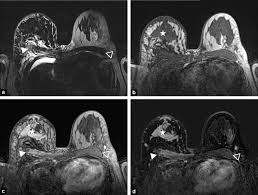

Признаки рака на МРТ молочных желез

Врачи диагностических центров СПб при поиске рака на МРТ молочных желез с контрастированием обращают внимание на следующие признаки:

- наличие самого образования, узла;

- неоднородность структуры опухоли;

- расположение новообразования вдоль протоков;

- лучистые контуры, как у звезды;

- реакция кожи, соседних тканей, сосков;

- патологические изменения в сосудистой сети;

- опухоль быстро накапливает и сбрасывает контраст.

Злокачественные и доброкачественные образования молочных желез имеют характерные MP-маммографические признаки, позволяющие проводить их дифференциальную диагностику. В заключении по результатам томографии врач может отметить выявленные:

- очаги контрастирования — очень мелкие участки поражения размером меньше 5 мм;

- контрастирования образования — это уже объемное поражение с выпирающим контуром;

- зоны контрастирования- участка ткани, который не является образованием или очагом с отрезками нормальной ткани или жира.

Признаками рака груди на снимках станет:

- наличие объемного образования с нечеткими контурами;

- наличие тканевой перестройки вокруг образования;

- поражения метастазами соседних органов;

- накапливание контрастного препарата сосудами опухоли;

- кольцевидный вид накопления контрастного вещества;

- быстрое поступление контраста и беспрепятственное его вымывание из опухоли.